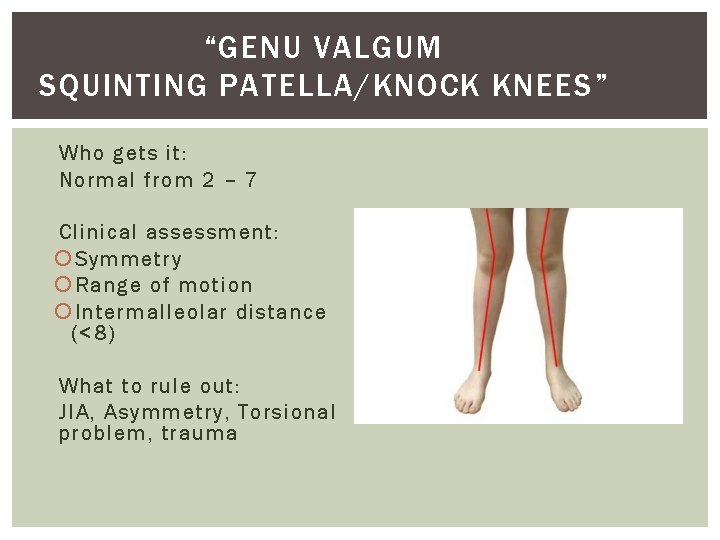

“GENU VALGUM SQUINTING PATELLA/KNOCK KNEES” Who gets it: Normal from 2 – 7 Clinical assessment : Symmetry Range of motion Intermalleolar distance (<8) What to rule out: JIA, Asymmetry, Torsional problem, trauma